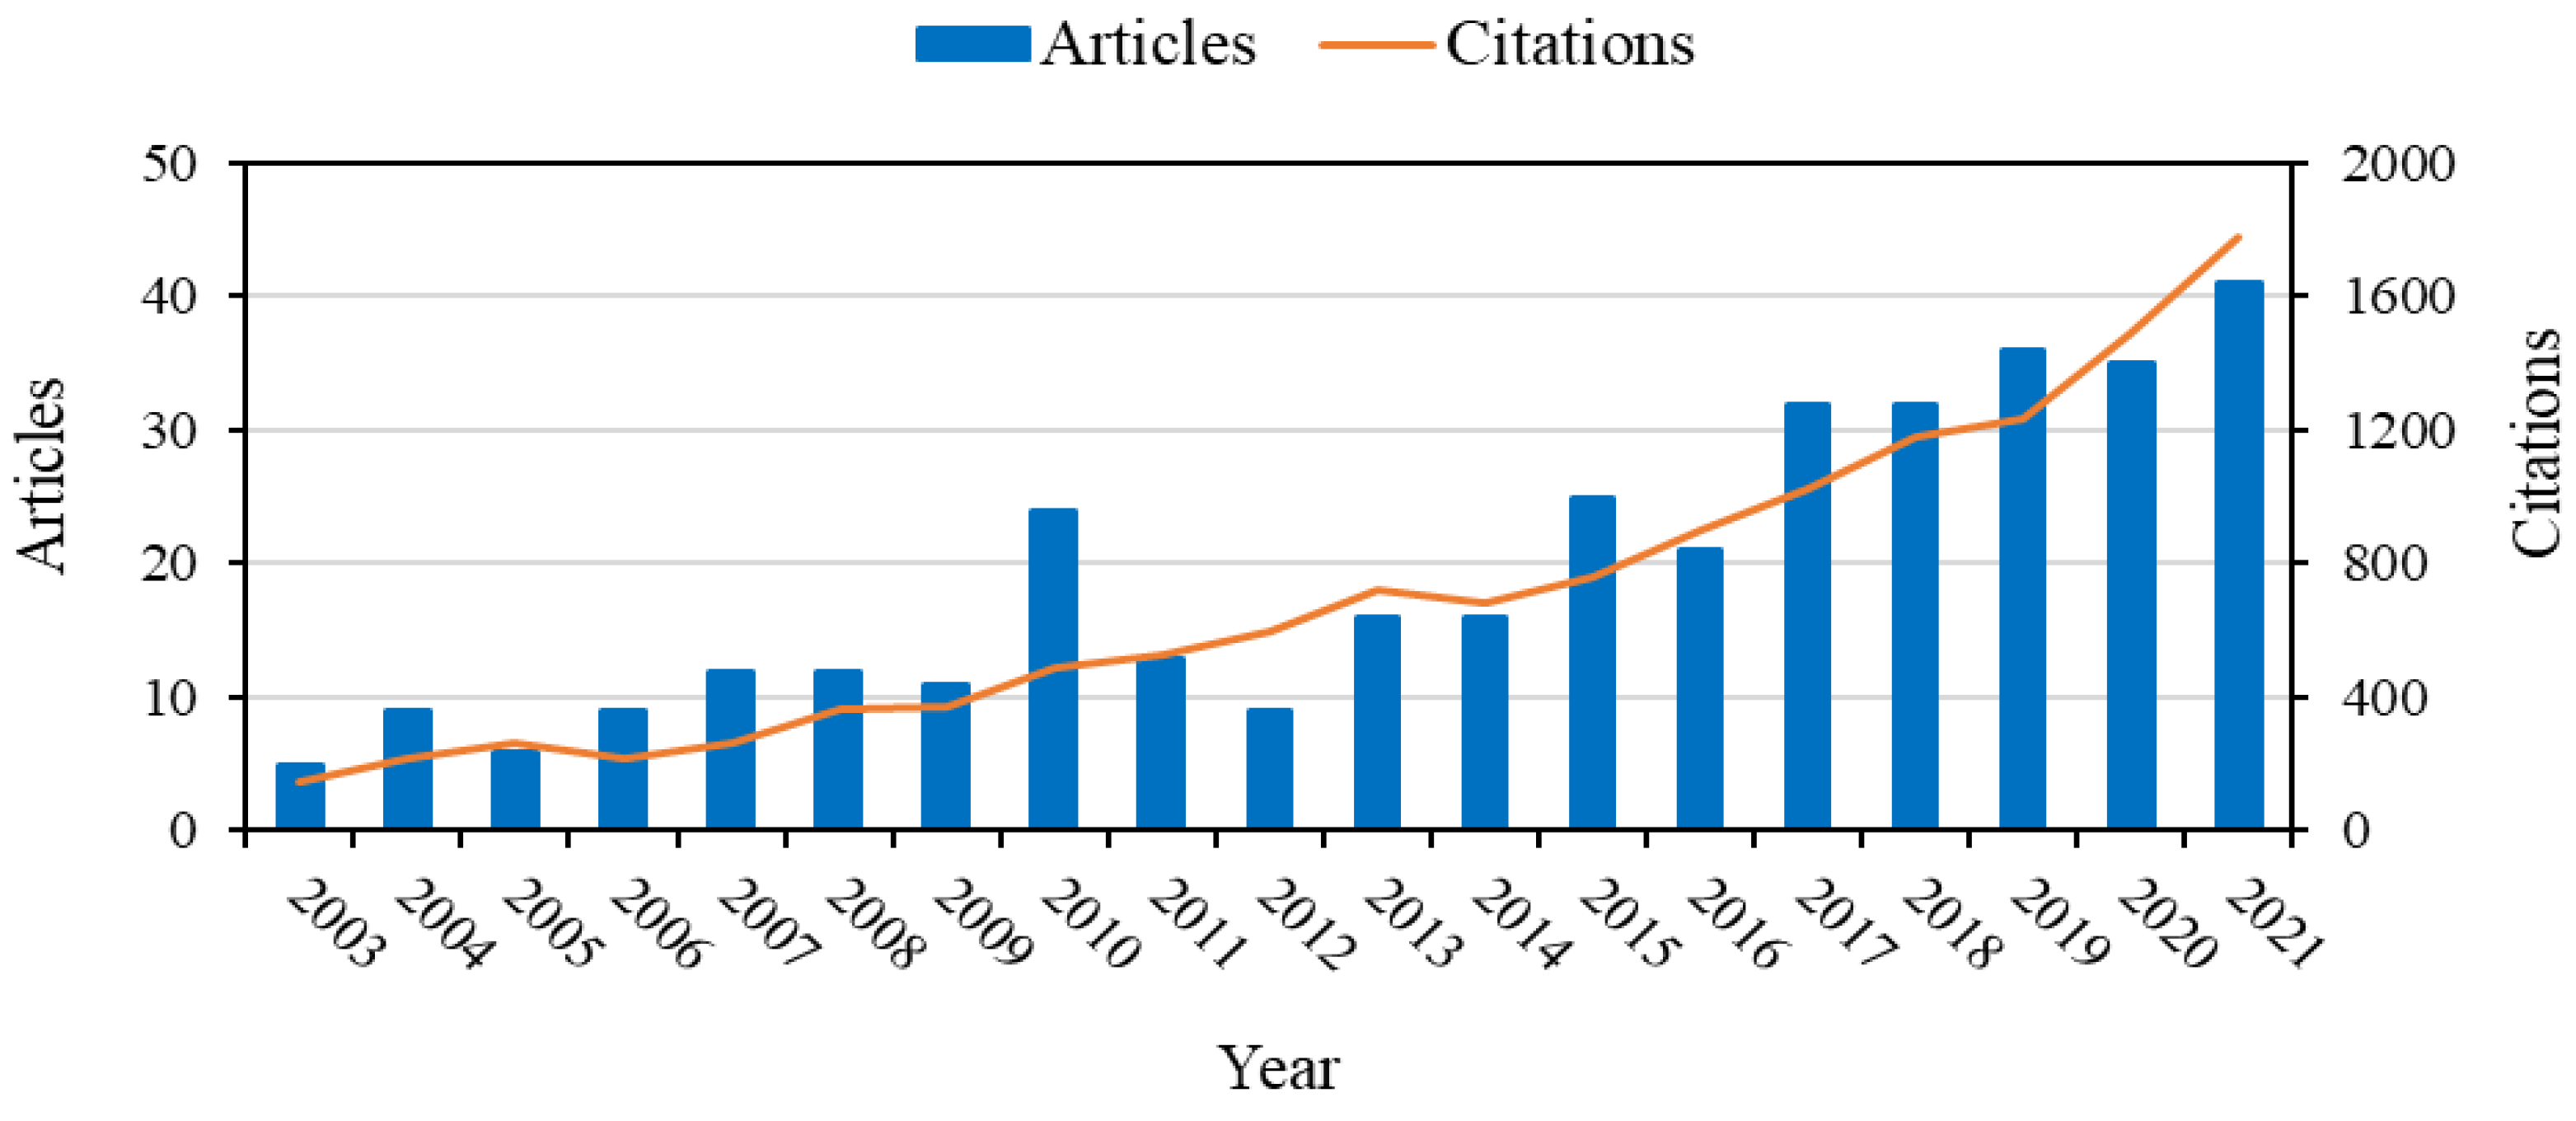

1. Introduction